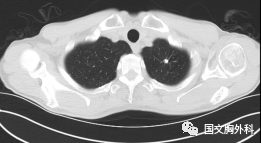

這個(gè)病人檢查胸部CT如圖3:根據(jù)影像學(xué)考慮是惡性腫瘤,行手術(shù)治療后病理回報(bào):“肺膿腫,合并炎癥纖維組織增生”,因此“肺占位”不代表就是惡性腫瘤,診斷金標(biāo)準(zhǔn)是病理診斷。如果檢查后發(fā)現(xiàn)“肺占位”先不要驚慌,及時(shí)就診請(qǐng)專(zhuān)科醫(yī)生會(huì)診指導(dǎo)治療才是關(guān)鍵。